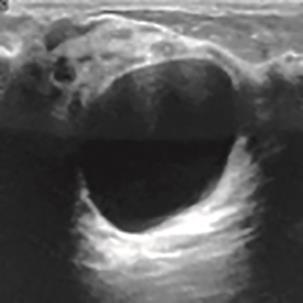

乳腺癌是全球女性最常见的恶性肿瘤之一,准确的病变分割对于乳腺癌的早期诊断与治疗具有重要意义。然而,由于病变形态的多样性以及超声成像机制的复杂性,现有基于深度学习的乳腺超声图像病变分割方法在分割准确性方面仍面临巨大挑战。为进一步提升乳腺超声图像中病变区域的分割精度,该文基于经典U-Net架构,提出了一种新型乳腺超声图像病变分割网络(CWSASKM-BBAM-Net)。首先,在网络中引入逐通道空间自适应选择核卷积模块(CWSASKM),根据不同通道的语义特征为每个空间位置自适应选择感受野大小,以增强多尺度信息的建模能力;然后,引入双向边界感知机制(BBAM),通过融合正向与反向注意力,对目标显著区域及其边界进行协同建模,同时逐步提升对非显著区域与病变区域的区分能力,以进一步强化边界信息的表达;最后,在3组公开乳腺超声图像数据集(BUSI、UDIAT和STU)上开展分割实验。结果表明:该方法在数据集BUSI上的杰卡德指数、精确率、召回率和Dice相似系数分别为71.97%、82.85%、81.40%和80.44%,较次优方法分别提升1.69、1.05、1.28和1.84个百分点;在数据集UDIAT上,这4项指标分别达到78.14%、88.31%、86.73%和86.10%,较次优方法分别提升了2.75、2.04、0.56和2.01个百分点;在外部数据集STU上,该方法也取得了优于其他方法的整体表现。实验结果表明,CWSASKM-BBAM-Net在乳腺超声图像分割任务中展现出更优的整体性能。